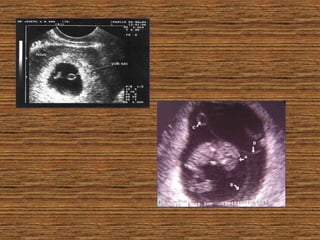

LA ECOGRAFIA